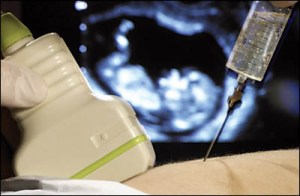

De la 17 saptamani de cand i s-a recomndata aceasta analiza, am cautat cu sotia mea solutii sau spitale care sa faca aceasta analiza gratis s-au la un cost mai mic (1.500-2.000 RON costa aceasta analiza). In urma unui articol in ziarul Evenimentul Zilei am gasit laboratorul GeneticLab, laborator care in urma unei tombole, acorda o analiza gratis pe luna pentru femeile care au un venit foarte mic sau deloc. Am aplicat la firma GeneticLab pentru sotia mea care avea nevoie de amniocenteza si am fost selectati pentru luna februarie castigatorii al acestei analize.

Amniocenteza, analiza esentiala pentru a depista acest sindrom (si nu numai pt. acest sindrom), este prin declaratia directorului CNAS, Dorin Ionescu, asigurata INTEGRAL de CNAS, prin comunicatul Spitalului Giulesti aceasta analiza este decontata doar partial (adica doar recoltarea lichidului amniotic in rest femeia sa mearga cu eprubeta la clinicile private sa ii fie analizata proba), o controverasa sau o enigma care nici astazi nu este elucidata. Eu si sotia mea, si ca noi foarte multi altii, suntem in mijlocul neintelegerii si lipsei de transparenta al celor care fac parte din sistemul medical romanesc.

3. Si eu am facut amniocenteza la domnul doctor Albu pe 27 mai 2014 si nu doare absolut deloc chiar si fara anestezie locala. De la aflarea rezultatului la dublu test – risc 1/106 trisomia 21 sl pana in ziua amniocentezei slabisem 3 kg de cate griji imi faceam , nu mai puteam dormi nici noaptea. Imi era frica de procedura in sine si de riscul de a pierde bebelusul , dar daca respecti tratamentul post amnio si sfaturile domnului doctor pericolul este extrem de redus. Domnul doctor Albu are foarte mare experienta in amnio. Acum sunt linistita,impacata si fericita ca bebelina este bine. Am zis ca o sa sfatuiesc si o sa indrum pe oricine este in aceeasi situatie cum am fost eu sa mearga cu incredere sa faca amniocenteza deoarece nu este o procedura asa de riscanta cum se vorbeste. Pretul este de 1200 ron cu trimitere de la medicul de familie dar linistea pe care ti-o da rezultatele nu se poate masura.Rezultatele vor veni mai repede decat o sa va spuna la cabinet.